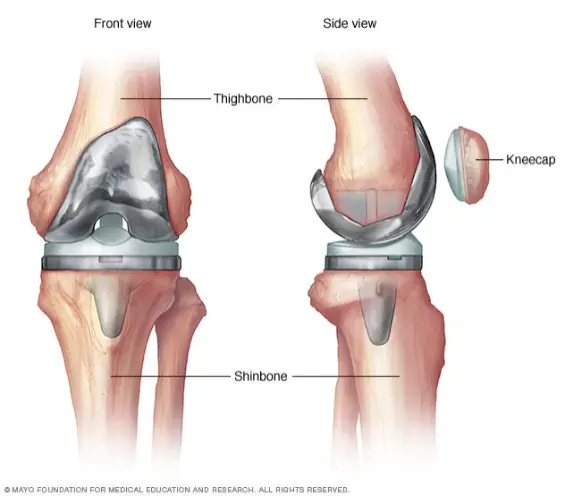

A joint replacement, or arthroplasty, is a surgical procedure that removes damaged or diseased parts of a joint (like hip, knee, shoulder) and replaces them with artificial components (prosthetics/implants) to relieve pain, improve movement, and restore function, typically caused by arthritis, injury, or tumors. The surgery involves implanting metal and plastic parts to mimic a healthy joint, allowing for smoother motion.

- Removal: Damaged bone and cartilage are removed from the joint surfaces.

- Replacement: Artificial components (prosthesis/implants) made of metal, plastic, or ceramic are inserted to replace the removed parts.

- Mechanism: Implants are designed with specialized porous surfaces that encourage natural bone to grow into the metal, creating a direct, durable, and, in some cases, stronger bond over time, allowing for enhanced load-bearing.

- Application: The concept is fundamental to modern, “cementless” total or partial knee arthroplasty, where no bone cement is used to fix the implant.